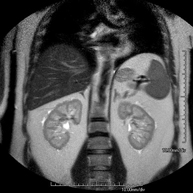

- Kidney MRI

This non-invasive diagnostic procedure uses an electromagnetic field and radio waves (from a transmitter and receiver) to acquire high-definition anatomical images of the kidneys. It is a radiation-free procedure. It is performed to study any localised injury in both kidneys. Paramagnetic contrast (gadolinium) is usually required to characterise the lesions.